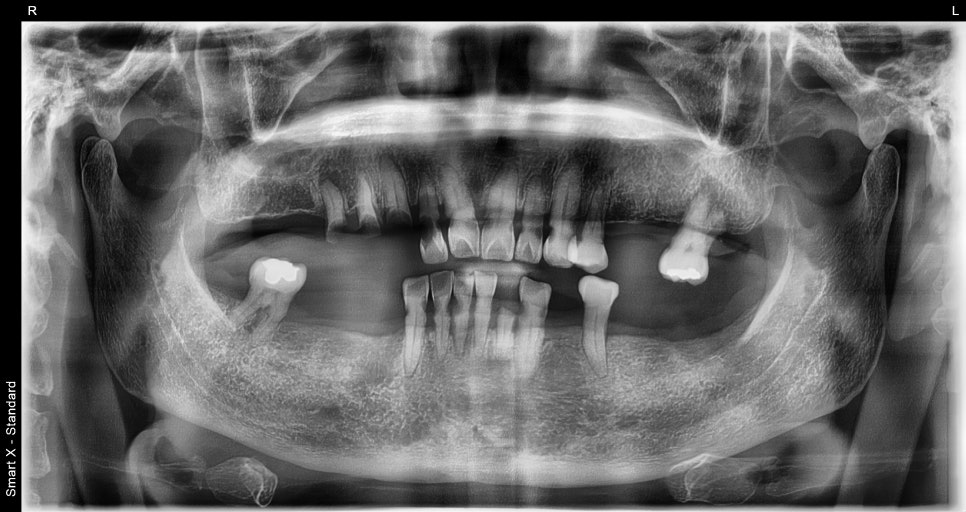

내원당시 상태

환자분은 30년 이상 치과 진료를 미루며

전체적인 치아 마모, 탈락, 잇몸 염증이

복합적으로 진행된 상태였습니다.

특히 어금니가 거의 모두 빠져 있어

저작 기능이 상실된 상황이었고

남아 있는 치아들도 마모가 심해 교합을

유지하기 어려웠습니다.

잇몸 사이에는 음식물이 끼면서

염증과 냄새가 반복적으로 발생했고

일상적인 식사에도 많은 불편이 있었습니다.

이런 경우에는 일부 치료로는 회복이 어렵기 때문에

무너진 교합과 잇몸 라인을 함께 재정비하는

전체임플란트가 필요한 케이스였습니다.

서울오브치과병원 임플란트 전

<수술 전>